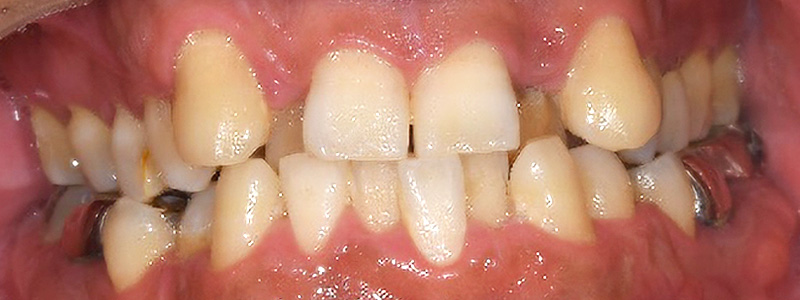

- 治療名

- 矯正・ジルコニアクラウン

- 治療内容

- がたつき改善のためマウスピースのみで矯正。ジルコニアクラウンを製作。

- 患者様

- 40代男性

- 治療期間

- 2年

- 費用

- ¥1,738,000

- 治療に対するリスク

- 後戻り

- 執刀医

- Dr.村尾